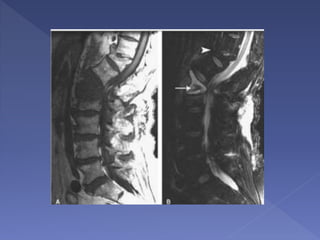

 MRI is the modality indicated for subsequent imaging

of patients with BFD as it best assesses the nature

and extent of spinal cord injury as well as any

associated disc and ligamentous injury